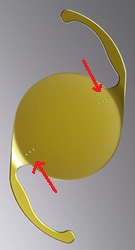

先日ハードレンズを処方した方の写真です。

先日ハードレンズを処方した方の写真です。